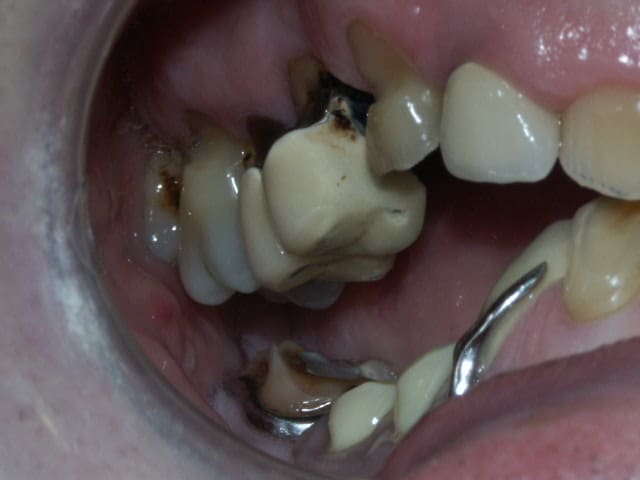

un cas très galère pour la rentrée... nouvelles photos et radios!!

Qu'est ce que je peux proposer comme plan de traitement?

j'avoue que je suis un peu paumé...

Le constat est le suivant, corrigez-moi si je me trompe:

on a eu des extractions non compensées à la mandibule qui ont provoquées des égressions des dents maxillaires postérieures.

une abrasion +++ du bloc antérieure avec égression "physiologique" au fur et à mesure de l'usure.

On a ainsi un décalage important (comme une marche d'escalier) de la courbe d'occlusion (Spee) entre le secteur antérieur et postérieur.

La difficulté de la thérapeutique consistera à rattraper le mieux possible ce décalage pour avoir une courbe d'occlusion "harmonieuse".